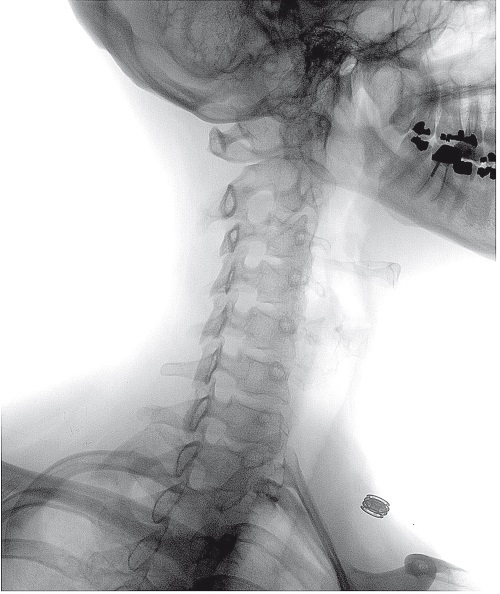

Метод лечения, разработанный в конце XIX века, который предполагает воздействие на позвоночник руками. Хотя иногда хиропрактики ограничиваются лечением болей в спине, многие из них берутся также исцелять своих пациентов и от целого ряда других распространенных болезней, например от астмы. Теория, лежащая в основе хиропрактики, гласит, что манипуляции на позвоночнике полезны с медицинской точки зрения, поскольку влияют на весь организм через нервную систему.

Хиропрактики, обычно лечащие проблемы с шеей или спиной с помощью манипуляций на позвоночнике, заняли столь прочное место в системе здравоохранения, что многие читатели, вероятно, даже удивились, увидев этот метод включенным в книгу о нетрадиционной медицине. Ведь многие обычные врачи рекомендуют своим больным обратиться к хиропрактику, а программы страхования, как правило, покрывают подобные процедуры. Это особенно актуально для Америки, где хиропрактиков больше всего и на лечение у них ежегодно тратится около 10 миллиардов долларов. Хиропрактика – не просто официальная часть американской системы здравоохранения, она продолжает набирать популярность: с 1970 по 1990 год число практикующих специалистов утроилось, а в 2002 году в Северной Америке их насчитывалось шестьдесят тысяч. Ожидалось, что к 2010 году их количество еще удвоится, тогда как обычных врачей станет больше всего на 16 %.